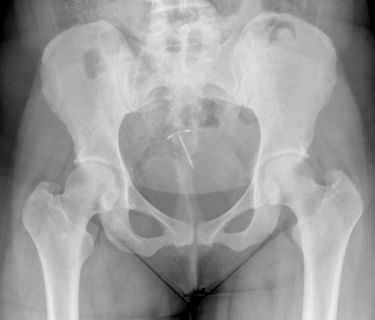

According to the Mirena lawsuit, on July 21, 2012, Samantha was hospitalized due to the severe pain in her lower right abdomen, where it was discovered that the IUD had perforated and migrated away from her uterus. Soon after, Samantha had the device removed from her vaginal canal but still remained in pain.

Several weeks after the removal, diagnostic testing revealed that when the Mirena IUD migrated away from the plaintiff’s uterus, it had damaged her lower abdomen. Medical records indicate that she experienced bowel adhesions to the uterus and bladder, which required surgical intervention to treat. On Aug. 27, 2012, Samantha underwent a laparoscopic procedure to treat the adhesions and had finally resolved her pain.